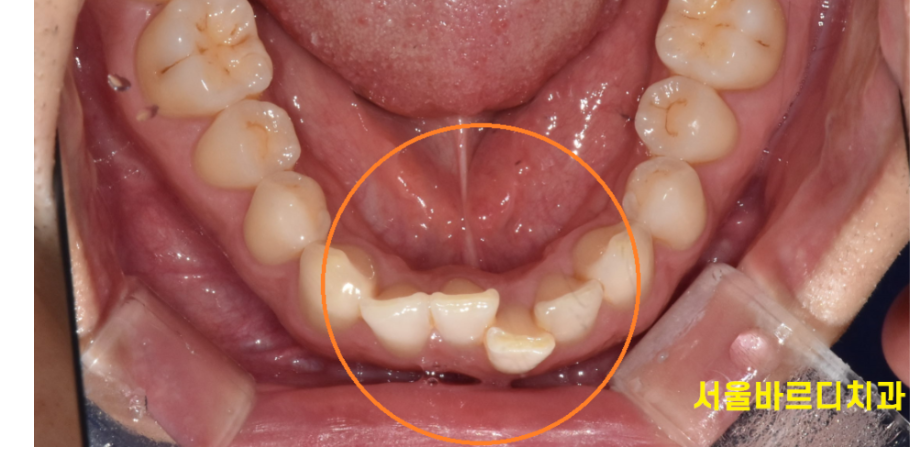

이렇게 삐뚤빼뚤한 치아 배열은

치아 공간 확보가 어려워 생기는 경우가 많습니다.